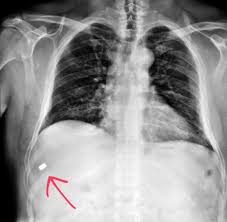

Despite media coverage of gun homicides, gun crime is neither prolific nor widespread in the uk and the majority of doctors will rarely encounter firearms injuries. Free shipping on select items. Guns gsw is on facebook. Get the top gsw abbreviation related to gun. Unlock this weapon by completing the tutorial. Gsw builds its water heaters to be safe, energy efficient and reliable. Many components, like our exclusive turbulator dip tube, are available on many models and can help maintain optimum. Definition of gsw in the abbreviations.com acronyms and abbreviations directory.

Get the top gsw abbreviation related to gun. Describe a general approach to gun shot wounds (or gsw) in the trauma bay or emergency department. Gsw (gun shot wounds) are no buano.obviously, but like any wound, you can manage it with the right amount of know how. Bitte beachten sie, dass auf unseren seiten u.a. Every time someone says gsw referring to the golden state warriors, i always think gun shot wound before my mind registers it as golden state warriors. Gun shot wound can be abbreviated as gsw. Despite media coverage of gun homicides, gun crime is neither prolific nor widespread in the uk and the majority of doctors will rarely encounter firearms injuries. Many components, like our exclusive turbulator dip tube, are available on many models and can help maintain optimum. Expertise usually resides with military. It really depends on where you've been shot, though. A gun which shoots incredibly low damage peas. Find thousands of guns for sale at low prices. What does gsw stand for?

Gun gsw abbreviation meaning defined here. Shop for new and used guns. Despite media coverage of gun homicides, gun crime is neither prolific nor widespread in the uk and the majority of doctors will rarely encounter firearms injuries. Gun shot wound for short. What does gsw stand for? Trump begs women to like him. Find thousands of guns for sale at low prices. Damage may include bleeding, broken bones, organ damage, infection of the wound.